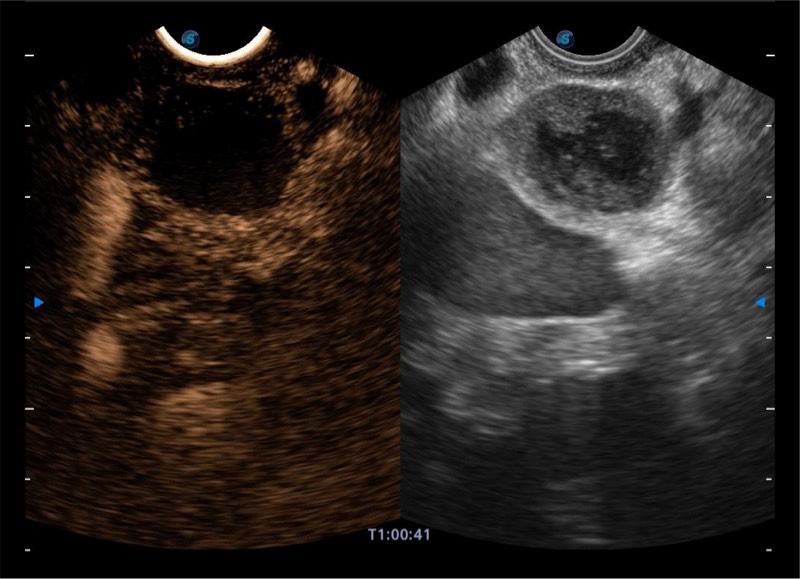

搭载百万级CMOS成像技术

及自主研发凸阵换能器,

可呈现优质的内镜和超声画面

基于二十年的超声技术积累,银河优越会提供了最新一代的独立超声主机,在提供高质量图像的同时满足多学科使用。具备常见多普勒技术并提供弹性成像、声学造影等高端影像技术。新一代传感器具有更强的抗干扰能力并减少图像伪影。

4-12MHZ宽频输出